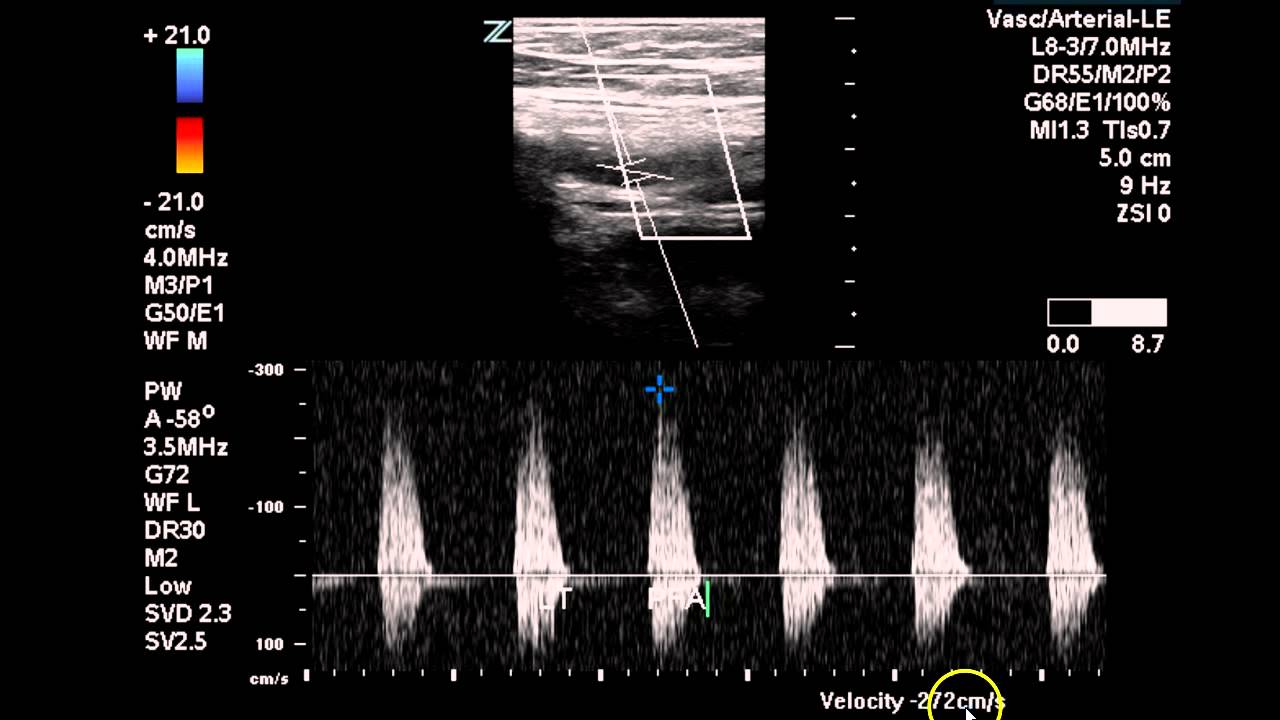

Der Duplex-Scan ist eine nicht-invasive Untersuchungsmethode, die Ultraschall verwendet, um den Blutfluss in den Arterien und Venen zu visualisieren und zu analysieren. Durch die Kombination von B-Bild-Sonographie und Doppler-Sonographie liefert er detaillierte Informationen über die Gefäßstruktur und die Blutflussgeschwindigkeit. Die Untersuchung spielt eine entscheidende Rolle bei der Diagnose verschiedener Gefäßerkrankungen.

Ein Duplex-Scan ist eine bildgebende Untersuchung, die den Blutfluss in den Gefäßen misst und sichtbar macht. Dabei wird eine Kombination aus herkömmlichem Ultraschall (B-Mode) und Doppler-Ultraschall verwendet. Der B-Mode liefert ein Bild der Gefäßstruktur, während der Doppler-Ultraschall die Geschwindigkeit und Richtung des Blutflusses misst.